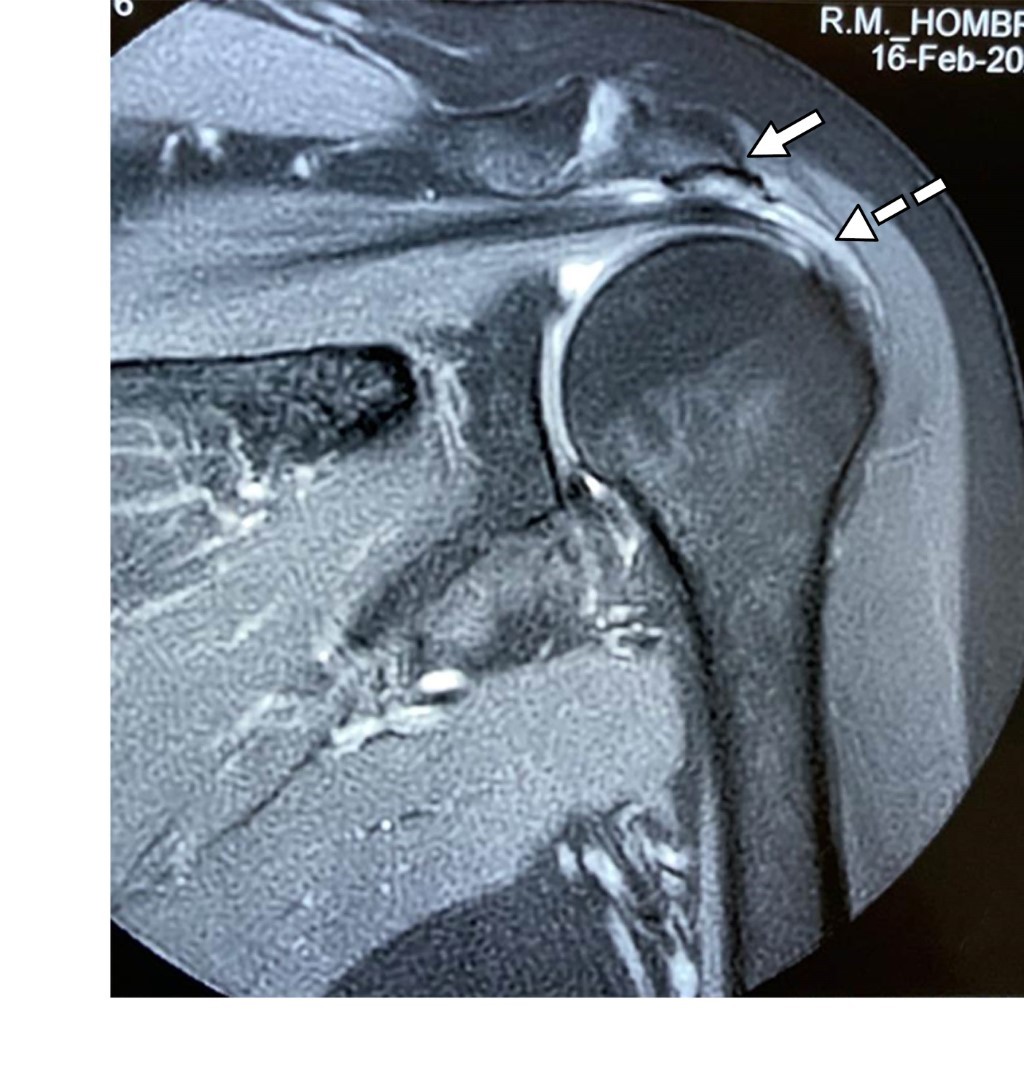

Se trata de paciente femenino de 69 con dolor en el hombro izquierdo de seis meses de evolución, principalmente con movimientos de abducción y flexión de codo. A la exploración de hombro izquierdo: arcos de movimiento limitados en abducción a 90° por dolor al igual que rotación externa de 45°, a la palpación masa dolorosa de aproximadamente 2 cm en borde interno del tendón de la porción larga del bíceps por debajo de la corredera bicipital. Prueba de choque de Neer, Hawkins y prueba de Yergason positivas; pruebas de inestabilidad de la articulación glenohumeral negativas. Las radiografías simples no mostraron hallazgos anormales. La resonancia magnética mostró: tendinosis del supraespinoso con ruptura parcial en su inserción, además de acromion tipo III con osteofitos subacromiales causantes de pinzamiento (Figura 1); en ponderación T2 se encontró tendinopatía de la porción larga del bíceps braquial con incremento de líquido en la corredera bicipital y quiste sinovial en su tercio proximal de 2.0 × 1.4 × 1.2 cm, con apariencia de estar encapsulada por la vaina del tendón bicipital (Figuras 2 y 3). Se canalizó a cirugía articular.

Figura 3